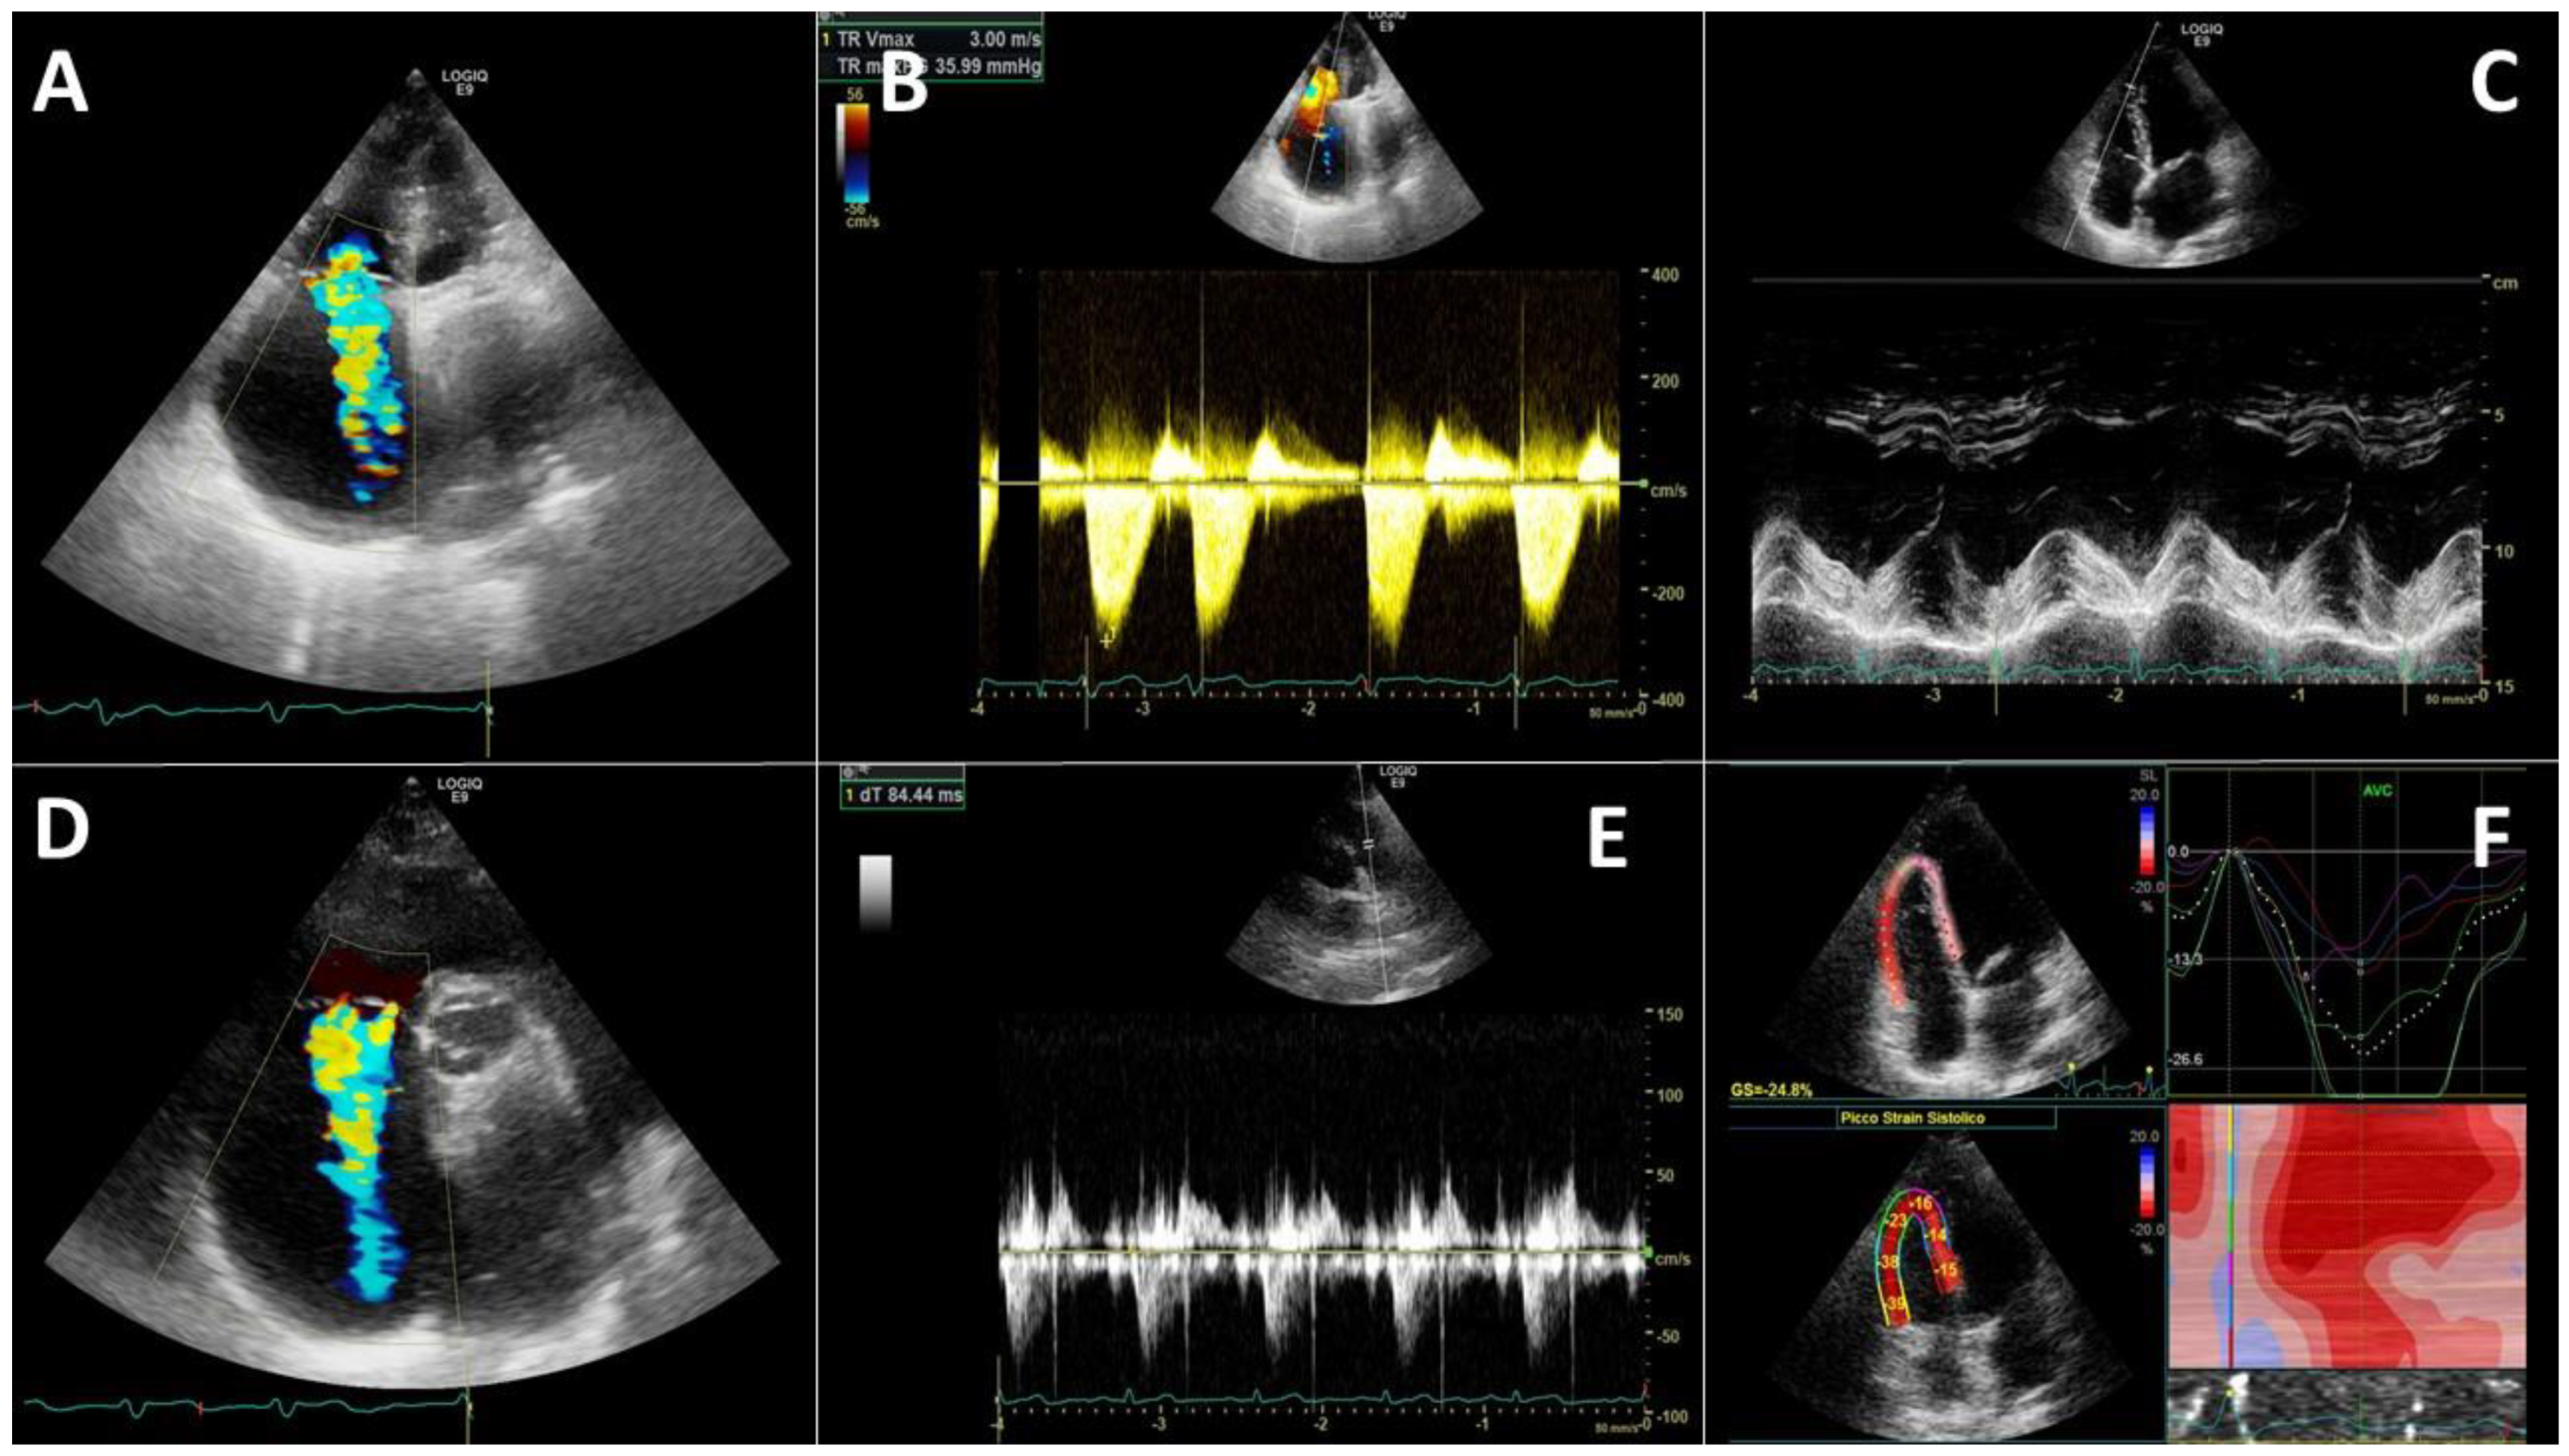

4.2. Right Heart Evaluation

8.1. Echocardiography Longitudinal Strain